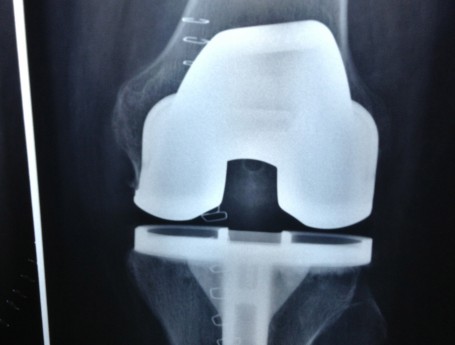

Revision Total Knee Replacement After Infection

• Revision Total Knee Replacement After Infection